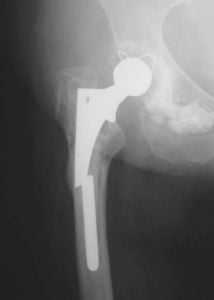

Признаки расшатывания эндопротеза тазобедренного сустава: как определить?

На сегодняшний день эндопротезирование крупных и мелких суставов является одним из самых популярных видов хирургического вмешательства в области травматологии и ортопедии. В западных клиниках объем таких операций составляет в совокупности более 1 миллиона в год. Отечественные клиники эндопротезирования пока в несколько раз отстают, предоставляя услуги по протезированию только 40-50 тысячам больных, хотя потребность в имплантатах гораздо выше.

Методика доказала на практике свою эффективность, однако, даже самые совершенные технологии могут в долгой перспективе привести к возникновению осложнений. Нестабильность частей эндопротеза - самая часто встречающаяся патология, которая может вызвать нежелательные последствия и привести к необходимости повторной операции.

Симптомы нестабильности протеза тазобедренного сустава

Можно выделить следующие признаки нестабильности эндопротеза тазобедренного сустава:

- Возникновение перманентной ноющей боли в суставе как во время ходьбы, так и в состоянии покоя. Зачастую болевые ощущения усиливаются ближе к ночи (во время сна).

- Потеря опоры для искусственного сустава.

- Общая слабость в нижних конечностях, быстрая утомляемость при ходьбе.

Все дело в том, что установленный имплантат влияет на движения тазобедренного сустава, как при тотальном эндопротезировании, таки при замене лишь части поврежденного сустава. В результате процесс восстановления костной ткани может замедлиться. Расшатывание ножки протеза в большинстве случаев приводит к развитию местного остеопороза. Таким образом, ограничивается подвижность самого эндопротеза.

К сожалению, современные научные и лабораторные исследования не смогли определить материал для протезов, которые бы не наносил абсолютно никакого вреда здоровью человека. В результате трения компонентов имплантата друг о друга мельчайшие частицы оседают в окружающих тканях, вызывая инфекционные процессы и отмирание тканей. Также может нарушится локальное кровообращение. Поэтому при появлении первых признаков расшатывания эндопротеза тазобедренного сустава следует немедленно обратиться за помощью к лечащему врачу.

Диагностика нестабильности протеза

При наступлении первых симптомов нестабильности эндопротеза тазобедренного сустава либо до появления таковых не будет лишним пройти курс диагностических мероприятий. Врач назначит следующие виды обследования:

- рентгенологическое исследование тазобедренного сустава;

- проведение анализа состояния костной ткани и ее плотности с помощью метода денситометрии;

- анализ процессов метаболизма в костной ткани.

В некоторых случаях назначение перечисленных выше мероприятий происходит сразу же после хирургического вмешательства. Особую опасность представляет изначальное наличие у пациента остеопороза, так как именно данная особенность костной ткани может спровоцировать нестабильность протеза после установки.